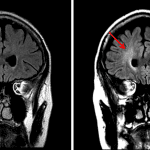

- Symmetric abnormal signal involving the bilateral globi pallidi including central T1/T2 isointensity with peripheral T2/FLAIR hyperintensity, thin discontinuous peripheral T1 hyperintensity, and peripheral enhancement

- Patchy areas of cortical enhancement in the medial left and inferior right cerebellar hemispheres with corresponding faint areas of T2/FLAIR hyperintensity

- Carbon monoxide toxicity

Symmetric abnormal signal in the bilateral globi pallidi with associated peripheral enhancement as well as patchy cortical enhancement involving the bilateral cerebellar hemispheres, for which the primary differential considerations are a toxic/metabolic process (including carbon monoxide poisoning, cyanide toxicity, and illicit drug use) and subacute infarcts.